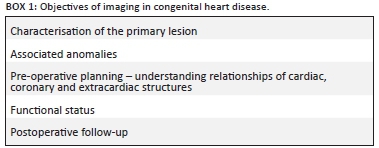

The objectives of imaging are addressed in Box 1.